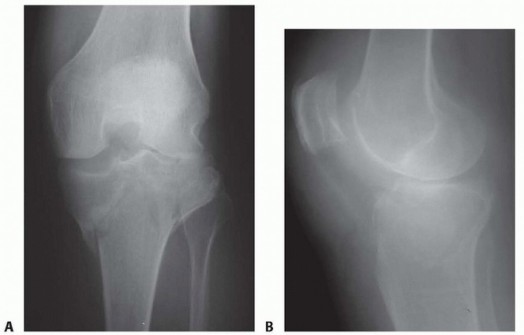

DEFINITION Fractures that occur above or around the femoral component of a total knee arthroplasty (TKA). The…